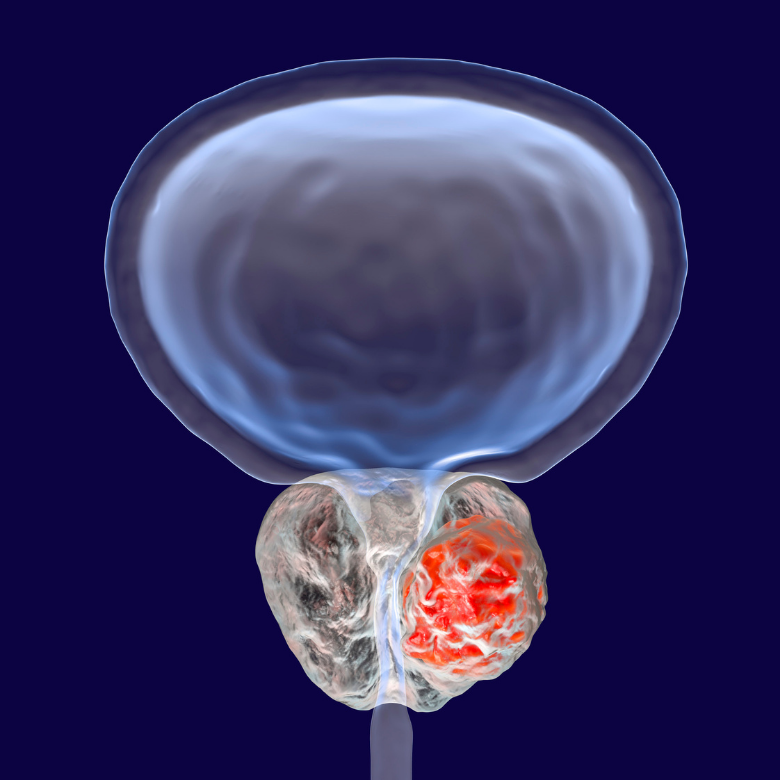

Erkeklerin özellikle de ileri yaşlarda sıklıkla karşılaştığı prostat kanseri tedavisinde modern yöntemler yüz güldürüyor! Özellikle de HIFU ile Ameliyatsız Prostat Kanseri Tedavisi yöntemi sunduğu yüksek tedavi başarı oranı ve konforlu uygulama olanaklarıyla her geçen gün daha popüler hale geliyor. Prostat kanserinin ameliyatsız tedavisini mümkün kılan HIFU hakkında tüm merak ettikleriniz sayfanın devamında tek tek sıralanıyor!

HIFU, yüksek yoğunluklu odaklanmış ultrason (High-Intensity Focused Ultrasound) kısaltmasıdır. Nokta atışı yöntem olarak da anılan HIFU sadece kanserli dokunun temizlenmesi ve vücutta herhangi bir tahribat olmamasını hedefleyen bir yöntemdir. Yüz estetiğinde de kullanılan HIFU yöntemi aynı zamanda doku ve hücreleri yenileyici bir işlemdir.

HIFU yöntemi genel anestezi altında uygulanır. Özel bir prob hastanın vücuduna sokulur ve kanserli prostat bölgesine yüksek frekanslı ultrason dalgaları gönderilir.Gönderilen ultrason dalgaları kanserli hücrelere yaklaşık 100 derecelik bir ısı uygular ve hücrelerin erimesini sağlar. Bu yöntem sırasında sadece kanserli hücreler hedeflenir. Vücuttaki diğer sağlıklı doku herhangi bir zarar görmemektedir.